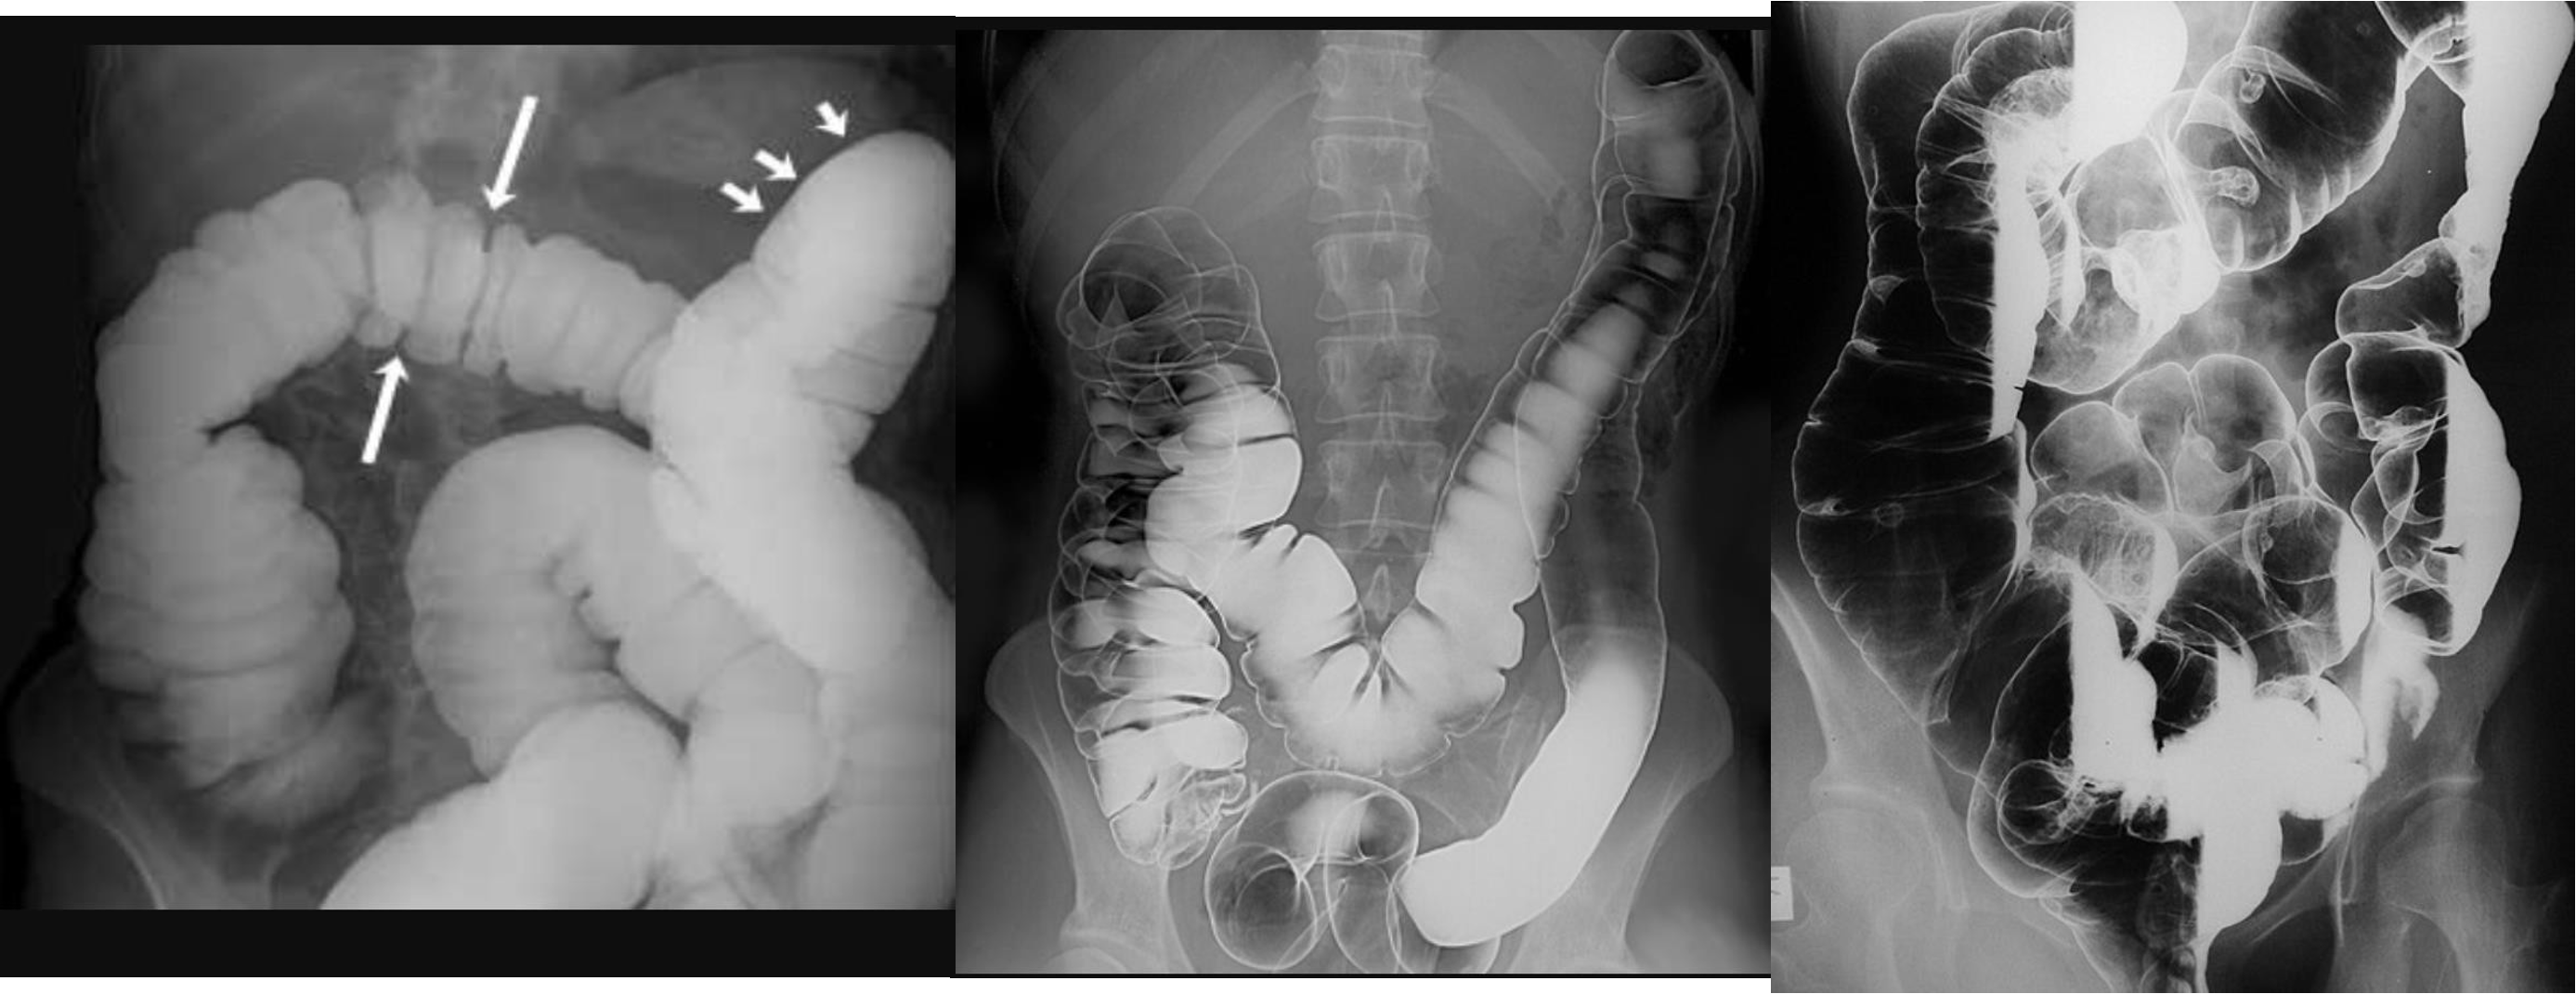

- erect - air fluid levels - should be not more than three - >5 significant 11 found -

- no free air under diaphgram - 8 fluid level, (evidence of bowel obstruction) (adhesion, hernia, IBD; Crohn, cancer, inturcucception, gallstones)

9 air fluids in large bowel - mucosal folds are not completed - highly suggestive of bowel obstruction

- 8 air fluid - small intestinal central - intistinal obstruction due adhesion - stack of coins. ++ NG tube aspiration relieve from vomitting

- dilated small bowel obstruction - stack of coins

- small bowel

2) large bowel - mucosal issnt complete periphery